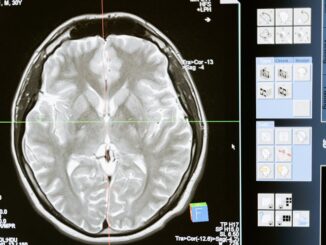

Navigating the AI Frontier in Healthcare: Bridging the Trust Chasm Artificial intelligence, AI for short, it’s not just a buzzword anymore, is it? It’s rapidly transforming nearly every industry you can think of. But nowhere […]